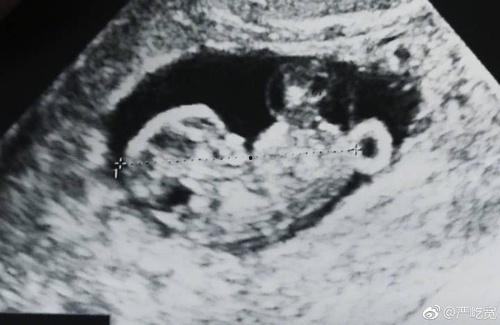

一、b超单子是什么?

首先,让我们来了解一下什么是b超单子。b超单子,全称为“超声波检查报告单”,是医生在进行超声波检查后,对受检者身体状况的书面报告。而在娱乐圈,b超单子却成为了明星们关注的焦点。